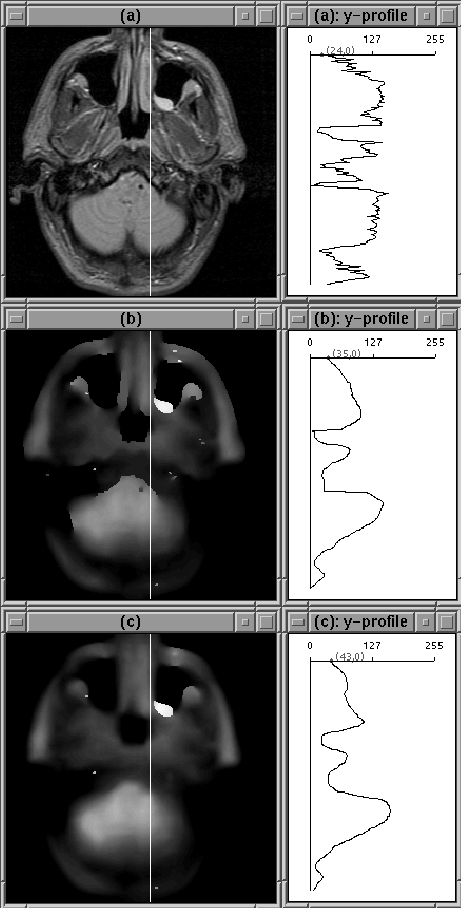

The 1D experiments are encouraging, but inconclusive. In some cases, filtering isolates the intracranial boundary, in others it does not. The image slice from the previous experiment was then filtered using the 2D filter. The results are shown in Figure 4.12 for 2 sets of filter parameters. Although the intensity of tissues outside the brain has been decreased, a simple threshold is unlikely to remove all those tissues. Still the intensity reduction is likely to simplify an intensity-based segmentation approach.

Figure 4.12: Images after 100 iterations of 2D diffusion. (a) Original Image. (b) Diffused image, . (c) Diffused image, . The filter has not attenuated the eye tissue as desired.

The image cross-sections shown in 4.12 show that a reasonable profile of RF inhomogeneity was not produced by the diffusion process. The filter parameters cannot be adjusted so that the filter simultaneously attenuates non-brain regions, tracks the edge of the brain, and profiles RF inhomogeneity.